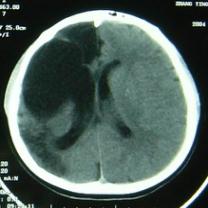

CT檢查:右額部見邊緣清晰的腦脊液密度區(qū),大小約82mm×52mm,與側(cè)腦室相溝通,內(nèi)側(cè)達(dá)中線,其內(nèi)可見帶狀分隔;右側(cè)顳頂葉及部分枕葉腦組織呈低密度改變,左側(cè)側(cè)腦室形態(tài)、大小正常,中線結(jié)構(gòu)尚居中(圖1)。

圖1 CT(①②)顯示右額部邊緣清晰的腦脊液密度區(qū)與側(cè)腦室相溝通,其內(nèi)可見帶狀分隔;右側(cè)顳頂葉及部分枕葉腦組織呈低密度改變